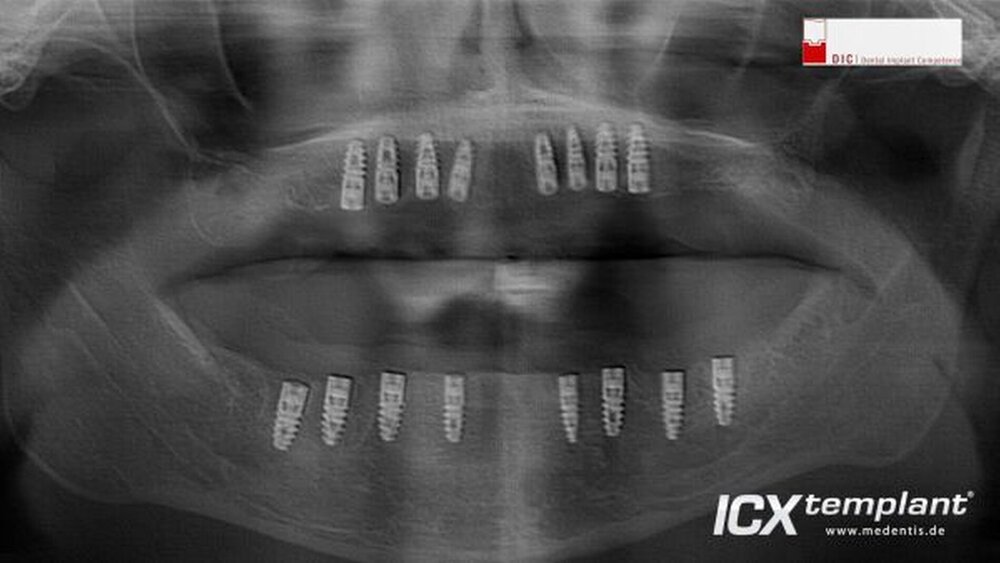

Implantation im zahnlosen Ober- und Unterkiefer

Die Operation wurde durchgeführt von Dr. Dr. Steffen Hohl (Buxtehude), Facharzt für Mund-, Kiefer- und plastische Gesichtschirurgie. Schwerpunkte: Implantologie, Oralchirurgie, Parodontologie, moderne 3D Verfahren, DIC / Dental Implant Competence.